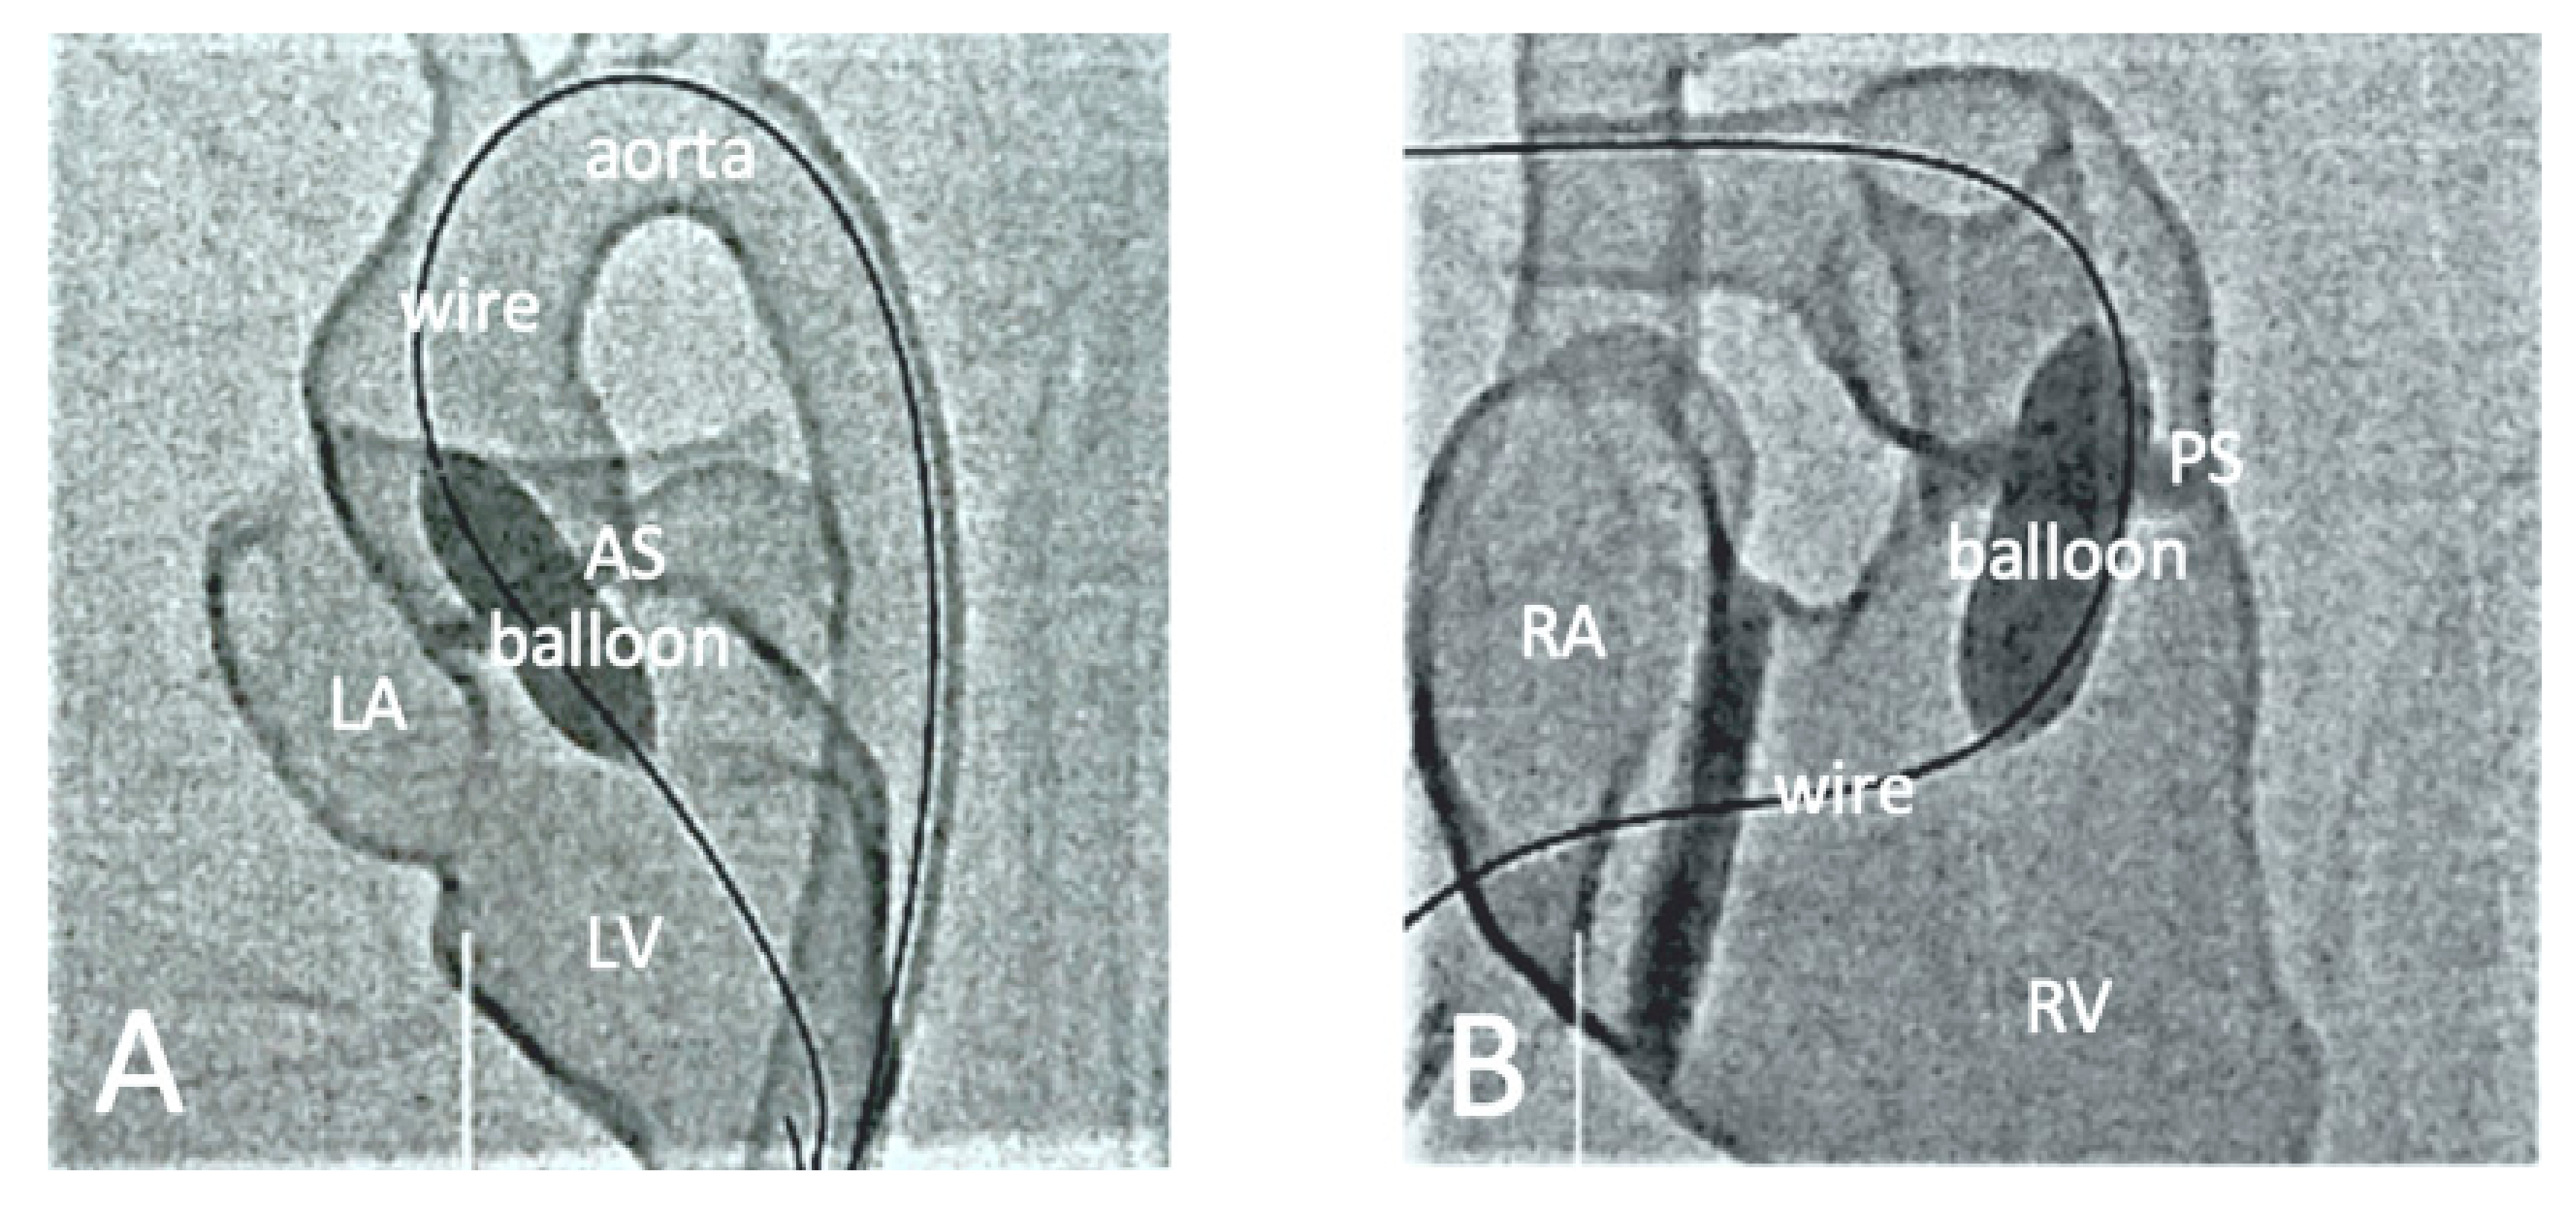

- Sun, Z.; Ng, C.K. Artificial intelligence (enhanced super-resolution generative adversarial network) for calcium deblooming in coronary computed tomography angiography: A feasibility study. Diagnostics 2022, 12, 991. [Google Scholar] [CrossRef]

- Sun, Z.; Ng, C.K. Finetuned super-resolution generative adversarial network (artificial intelligence) model for calcium deblooming in coronary computed tomography angiography. J. Pers. Med. 2022, 12, 1354. [Google Scholar] [CrossRef]